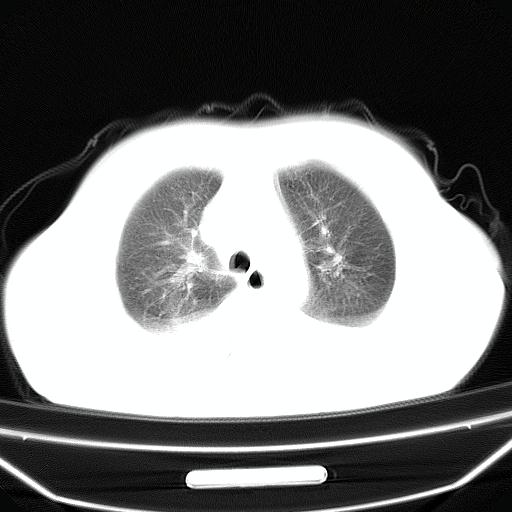

以下是引用jiangjing在2008-4-20 10:43:00的发言:[br]结合病史支持 冠心病[冠状动脉钙化],心功能不全,肺淤血、肺水肿,双侧胸腔与斜裂积液

以下是引用liuyue在2008-4-19 22:25:00的发言:[br]先考虑:1.心衰伴肺水肿、双侧胸腔积液、叶间积液、双下肺不完全性肺不张; [br] 2.冠状动脉粥样硬化。

以下是引用lijuanln在2008-4-19 23:05:00的发言:[br]两侧胸腔积液,肺水肿[br]心包积液[br]提示心衰